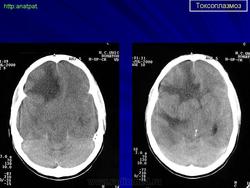

Пато морфологи я. Патоморфологические изменения при приобретенном токсоплазмозе изучены в экспериментах на животных. Установлено, что в центральной нервной системе развиваются явления некротического перивентрикулита, мелкие очаги некроза в субкортикальном белом веществе. В сосудах головного мозга, мягкой мозговой оболочки и хориоидальных сплетениях отмечаются признаки серозно-пролиферативного воспаления. Обнаруживаются также глазные патологоанатомические изменения (типа ретинита, хориоидита, иридоциклита) и изменения во внутренних органах (сердце, легкие, печень, селезенка).

Врожденный токсоплазмоз чаще, чем приобретенный, приводит к летальному исходу. В головном мозге умерших обнаруживаются более или менее значительные очаги обызвествления, участки размягчения мозгового вещества, полости, заполненные жидкостью. Как правило, отмечается гидроцефалия, обусловленная воспалительной и рубцовой облитерацией водопровода среднего мозга, отверстий Люшка или других участков ликворных путей. Истон-чение вещества полушарий мозга может достигать степени их полного исчезновения.

Особенно характерна триада симптомов: хореоретинит, гидроцефалия, очаги обызвествления в головном мозге. Кроме того, отмечаются менингеальные знаки, тонические и клонические судороги, парезы, параличи, олигофрения.

Неврологические симптомы могут сочетаться с пневмонией, миокардитом, гепатоспленомегалией, с выраженной желтухой. В спинномозговой жидкости отмечается лимфоцитарный плеоцитоз (до 500 • 106 в 1 л), ксантохромия (“канареечный” ликвор). На рентгенограмме черепа обнаруживаются обызвествления в глубинных отделах головного мозга, сосудистых сплетениях. Как и приобретенный, врожденный токсоплазмоз может протекать остро, подостро и хронически.

Церебральный токсоплазмоз.

Церебральный токсоплазмоз